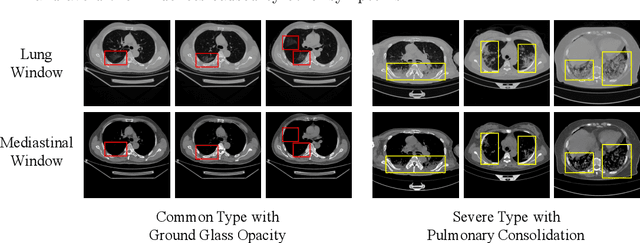

Abstract:Since the pandemic of COVID-19, several deep learning methods were proposed to analyze the chest Computed Tomography (CT) for diagnosis. In the current situation, the disease course classification is significant for medical personnel to decide the treatment. Most previous deep-learning-based methods extract features observed from the lung window. However, it has been proved that some appearances related to diagnosis can be observed better from the mediastinal window rather than the lung window, e.g., the pulmonary consolidation happens more in severe symptoms. In this paper, we propose a novel Dual Window RCNN Network (DWRNet), which mainly learns the distinctive features from the successive mediastinal window. Regarding the features extracted from the lung window, we introduce the Lung Window Attention Block (LWA Block) to pay additional attention to them for enhancing the mediastinal-window features. Moreover, instead of picking up specific slices from the whole CT slices, we use a Recurrent CNN and analyze successive slices as videos. Experimental results show that the fused and representative features improve the predictions of disease course by reaching the accuracy of 90.57%, against the baseline with an accuracy of 84.86%. Ablation studies demonstrate that combined dual window features are more efficient than lung-window features alone, while paying attention to lung-window features can improve the model's stability.